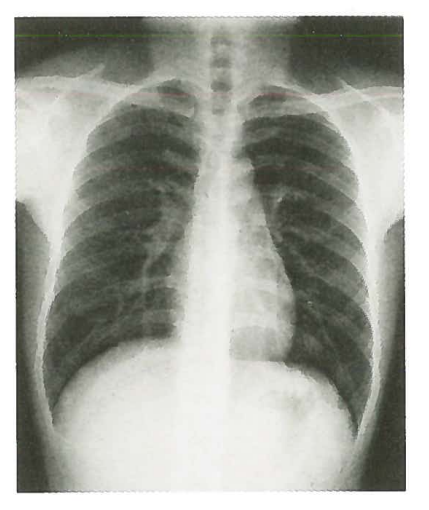

X射线成像是一个覆盖图像,即从X射线照射部分的前后到后面的所有图像的叠加,就像“感应眼”的角度。因此,X射线成像也称为荧光镜检查。例如,用于学校体格检查的“胸部荧光镜”项目,公务员和公共机构的参加体格检查是指胸部来回的X射线成像,但它不显示电影中的图像,成像板和平板电脑。在检测器中,它直接在荧光屏幕上显示以实时观察。下图是胸部来回的X射线图像,这表明胸部的所有组织结构都叠加在图像中。

图片来自第九版的Renwei医学成像